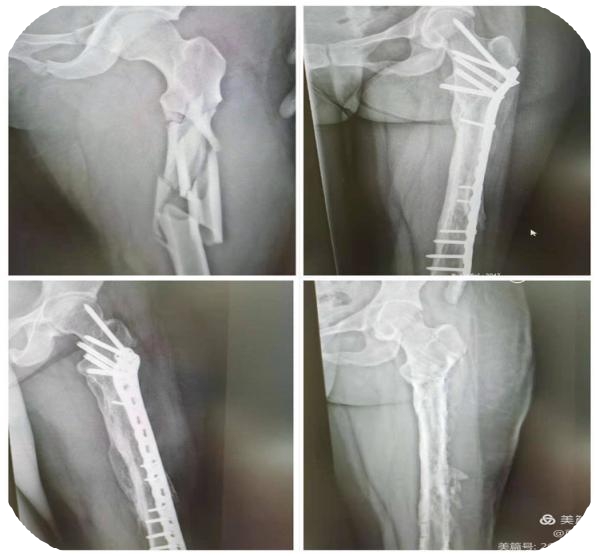

股骨粉碎性骨折,行复位内固定术

患者股骨粉碎性骨折,行复位内固定术,手术效果好,恢复满意